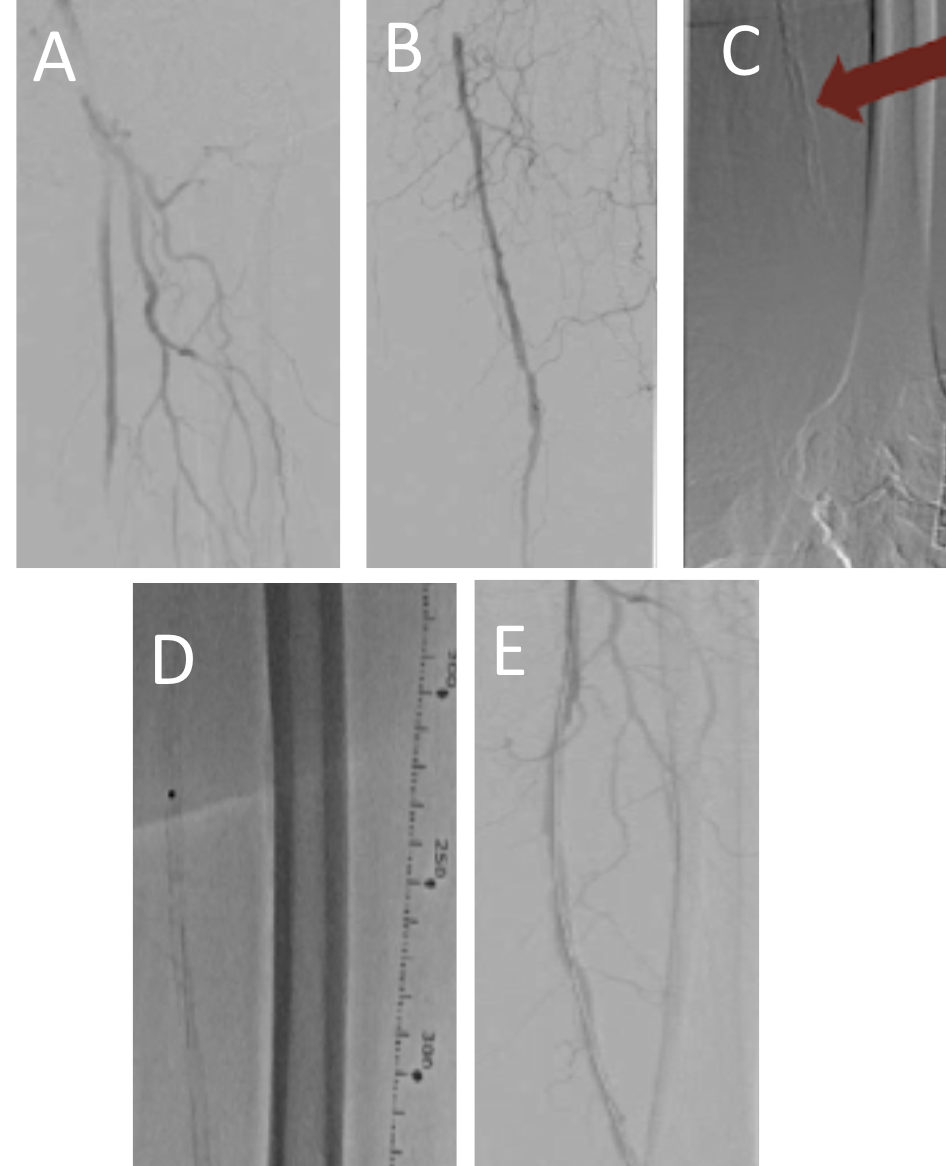

Access was obtained in the contralateral groin; a 7F Destination 45-cm sheath (Terumo) was placed in the left common femoral artery and diagnostic angiography was performed (Figures 1A-C and Videos 1A and 1B). Attempts at crossing with antegrade wire escalation and accompanying supportive microcatheters failed. Next, we prepared a 2.3 Turbo-Power laser (Philips) at a fluency of 60 mJ/mm² and a rate of 80 Hz. We placed the laser adjacent to the calcified CTO and retracted the wire into the laser catheter (of note, it is important to avoid using the laser on the hydrophilic portion of the wire as the wire tip can break). Gentle forward pressure with the laser was applied for a total of 2 minutes during therapy. The laser treatment resulted in easy wire passage through the CTO with a 0.014-inch hydrophilic tipped wire (Figure 1D). Next, 2 passes with the laser for plaque debulking were performed. Despite the laser atherectomy, a standard balloon would still not fully expand, so a 5 x 60-mm Shockwave intravascular lithotripsy balloon (Shockwave Medical) was utilized at 4 atmospheres with good expansion. Finally, a drug-coated balloon was deployed in the treated segment with good results (Figure 1E, Videos 1C and 1D). The patient’s wounds healed after 2 months of follow-up and wound care.